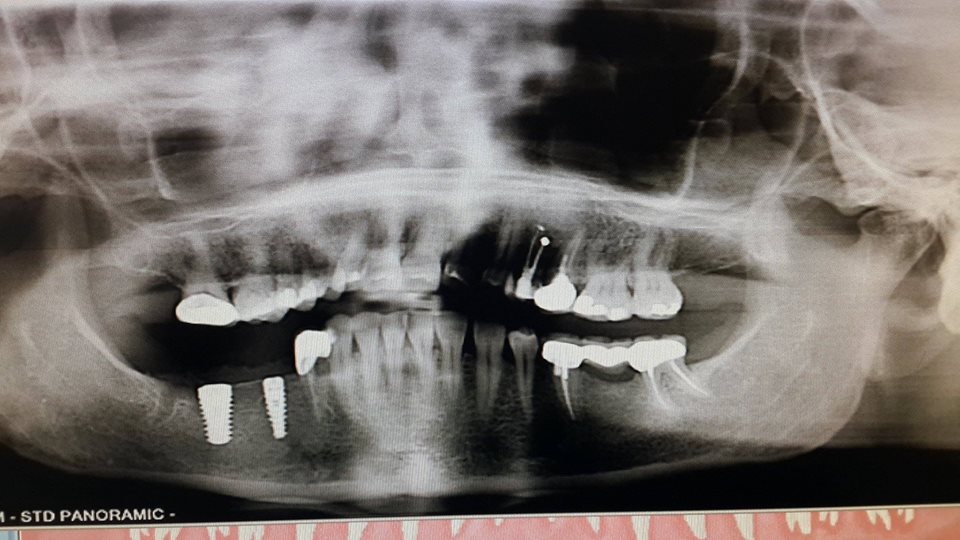

Implantation of the chewing tooth

A large-sized implant, 6×13 mm, was used to replace the recently removed 47th tooth.